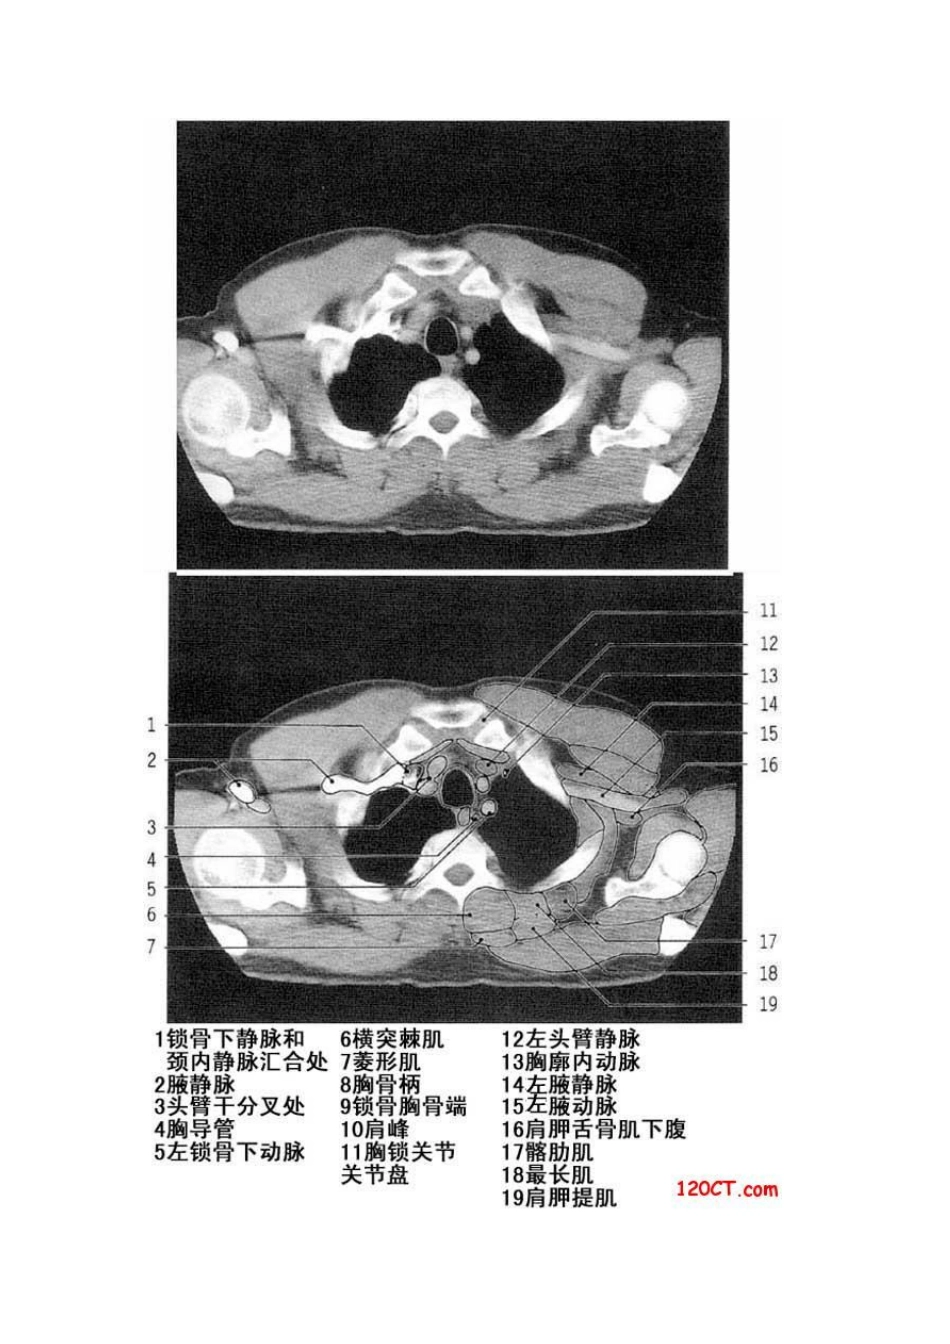

胸部CT解剖(软组织窗)